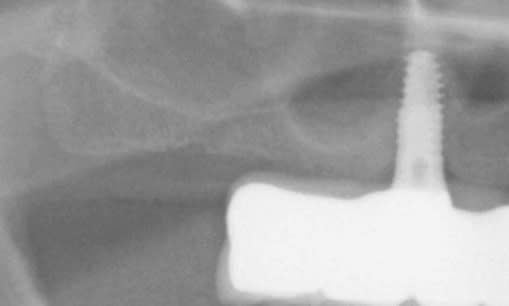

je dirais même mieux le meilleur relevé de sinus c'est pas de relevé de sinus

Implant dans septum sinusien ps2ffz - Eugenol

Screenshot873 iadlnk - Eugenol

3mos post op gppo6y - Eugenol

Pre op rxb7lo - Eugenol